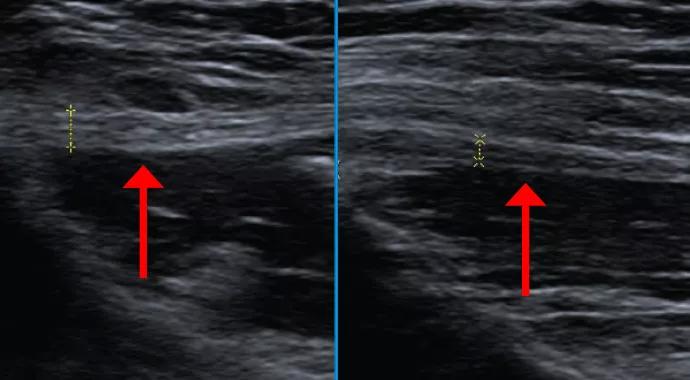

Cleveland Clinic sports health orthopaedic surgeon James Rosneck, MD, referred the patient for dedicated ultrasound neurography, which demonstrated asymmetric thickening of the left femoral cutaneous nerve just distal to the left anterior-superior iliac spine, where there was associated tenderness. Figure 1 contrasts a longitudinal view of the abnormally thickened lateral femoral cutaneous nerve (left image) with a longitudinal view of the contralateral normal nerve (right image). Figure 2 demonstrates the same side-to-side difference in the transverse plane.

Figure 1. Longitudinal views on ultrasound neurography showing an abnormally thickened lateral femoral cutaneous nerve (arrow, left image) in contrast with the contralateral normal nerve (arrow, right image). Figure 2. Transverse views on ultrasound neurography demonstrating the same side-to-side difference as in Figure 1.

Figure 1. Longitudinal views on ultrasound neurography showing an abnormally thickened lateral femoral cutaneous nerve (arrow, left image) in contrast with the contralateral normal nerve (arrow, right image).